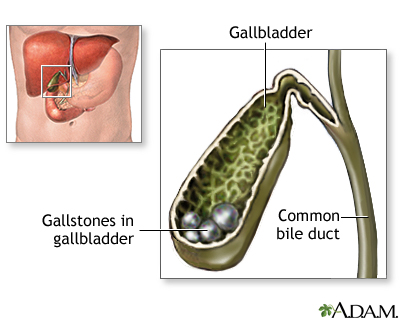

Gallstones are hard deposits that form inside the gallbladder. These may be as small as a grain of sand or as large as a golf ball.

- Stones made of cholesterol -- This is the most common type. Cholesterol gallstones are not related to the cholesterol level in the blood. In most cases, they are not visible on CT scans but are visible on a sonogram (ultrasound) of the abdomen.

- Stones made of bilirubin -- These are called pigment stones. They occur when there is too much bilirubin in the bile, often due to too many red blood cells being destroyed.

However, if a large stone blocks a tube or duct that drains the gallbladder, you may have a cramping pain in the middle to right upper abdomen. This is called biliary colic. The pain goes away if the stone passes into the first part of the small intestine.

ERCP and a procedure called a sphincterotomy may be done to find or treat gallstones in the common bile duct.

Blockage by gallstones may cause swelling or infection in the:

- Gallbladder (cholecystitis)

- Tube that carries bile from the liver to the gallbladder and intestines (cholangitis)